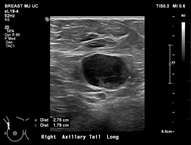

Features concerning for malignancy include round shape, increased cortical thickness and loss of fatty hilum1. The relationship of the lymph node cortex to hilum can be used to classify lymph node morphology and likelihood of malignancy. As the cortical thickness increases, there are reciprocal changes in the hilum beginning with hilar effacement and progressing to absence or replacement of the lymph node hilum2,3. Cortical thickening (figure 3) is considered the earliest morphologic change associated with malignancy; however, this finding is nonspecific with a low positive predictive value1-3. Absent/replaced hilum (figure 4) is the most specific for malignancy with a positive predictive value of 58-97%2.